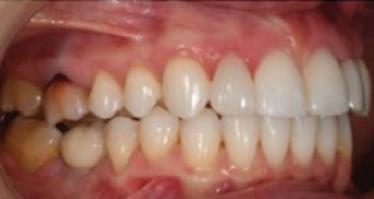

планта бе поставена временна коронка (фиг. 10 и 11), докато бъде изготвена окончателна та. Бе постигнат отличен кра ен резултат. Меките тъка ни около импланта напълно заздравяха, което доприне се за перфектната хармония между бяла и розова естетика (фиг. 12–15).

Dental Tribune Bulgarian Edition / октомври 2022 г.18 воначалния план. Тези пробле ми бяха адресирани чрез допъл нителна поръчка на алайнери с торк контрол и зададено екст рудиране на задните зъби с цел установяване на добри оклузал ни контакти в дисталните об ласти, като бяха предвидени и оптимизирани атачмънти с контрол над корените за корекция на ангулацията на макси ларните резци (фиг. 8). Резултати от лечението Панорамната рентгено графия след ортодонтското лечение показа благоприятна паралелна позиция на съседни те зъби, подходяща за поставя не на имплант в областта на #22, както и конвергенция на ко рените на зъби #44 и 45 (фиг. 9), но преценихме, че няма да от деляме допълнително лечебно време за коригирането ѝ поради факта, че пациентката бе мно го доволна от постигнатия до момента резултат. След при ключване на лечението бяха постигнати отлични взаимо отношения клас I при мола рите и канините, а срединни

съвпадаха. Върху им

но